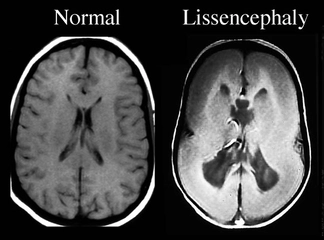

Epilepsi, merkezi sinir sistemini etkileyen ve tekrarlayan nöbetlerle karakterize bir durumdur. Nöbetler, beyindeki anormal elektriksel aktiviteden kaynaklanır ve çeşitli fiziksel ve psikolojik belirtilerle kendini gösterebilir. Bu makalede, epilepsinin göz kayması ile ilişkili belirtileri ve tedavi yöntemleri ele alınacaktır. Epilepsi Nedir?Epilepsi, beyinde anormal elektriksel aktivitelerin meydana gelmesi sonucu oluşan ve nöbetlerle kendini gösteren bir durumdur. Nöbetler, kişinin bilinç kaybı, kasılmalar ve göz kayması gibi belirtilerle ortaya çıkabilir. Göz Kayması Nedir?Göz kayması, gözlerin normalden saparak farklı yönlere hareket etmesi durumudur. Bu durum, göz kaslarının koordinasyonundaki bozukluklardan kaynaklanabilir. Epilepsi nöbetleri sırasında göz kayması sıkça gözlemlenen bir belirtidir. Epilepsi Göz Kayması BelirtileriEpilepsi göz kayması, çeşitli belirtilerle birlikte ortaya çıkabilir. Bu belirtiler arasında şunlar yer alır:

Bu belirtiler, epileptik nöbetin türüne bağlı olarak değişiklik gösterebilir. Epilepsinin Göz Kaymasına EtkisiEpilepsi, göz kaslarının kontrolünü etkileyebilir ve bu da göz kaymasına yol açabilir. Nöbet sırasında beyindeki elektriksel aktivite, göz kaslarının ani ve kontrolsüz bir şekilde kasılmasına neden olabilir. Bu durum, gözlerin anormal yönlere kaymasına yol açar. Epilepsi Göz Kayması Tedavi YöntemleriEpilepsi tedavisi, bireyin durumuna ve nöbet türüne bağlı olarak değişiklik gösterebilir. Tedavi yöntemleri arasında şunlar bulunmaktadır: